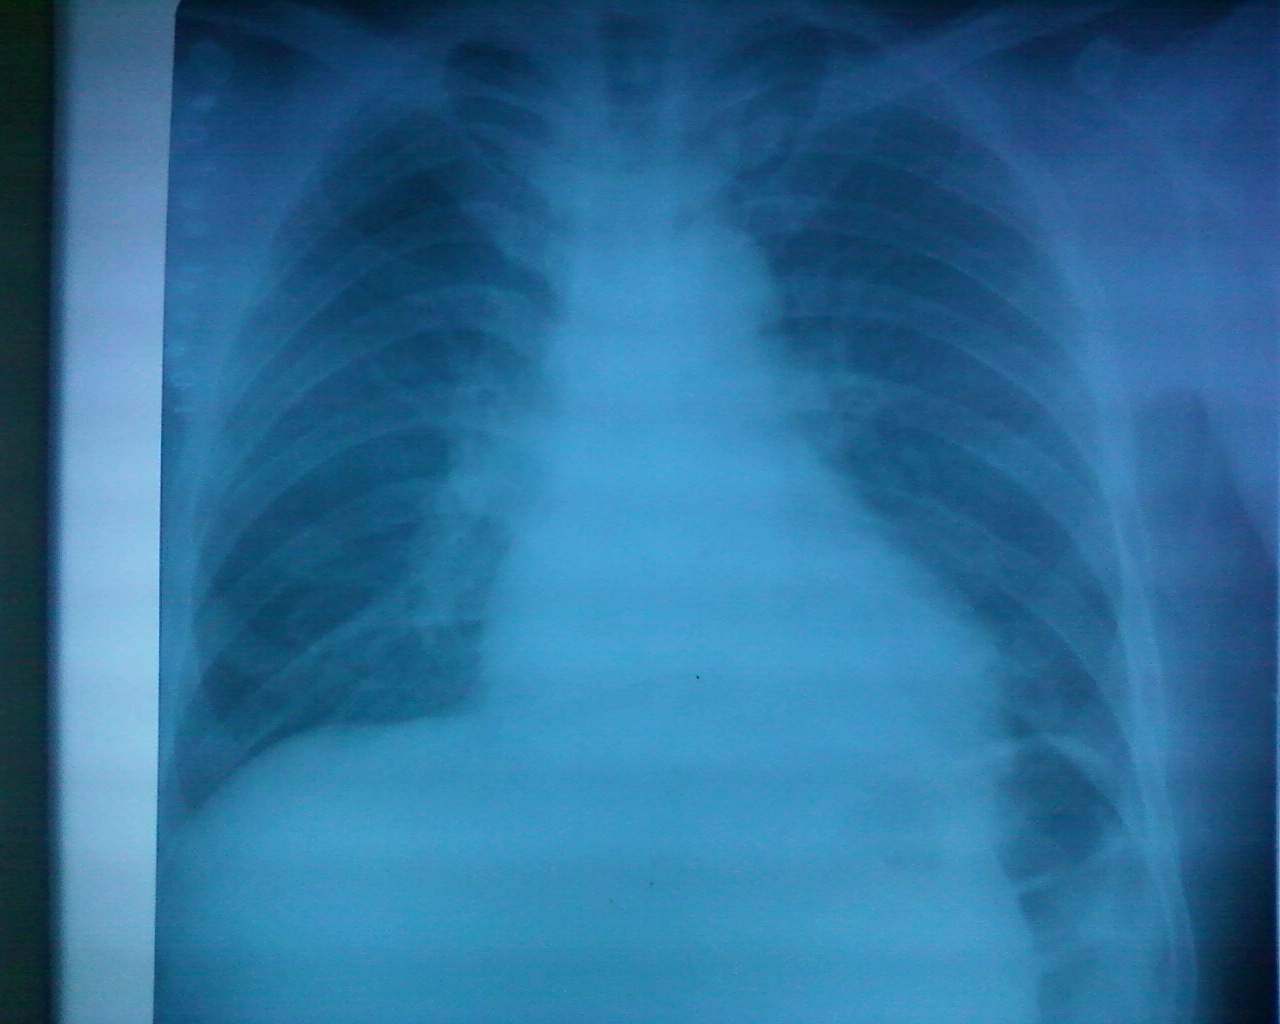

左侧间位结肠,心脏增大。右室增大为主。请问间位结肠有什么临床意义?

间位结肠是指结肠(多为肝曲)由肝前间隙或肝后间隙进入肝脏与膈之间,可无症状,可引起右季肋部隐痛、腹胀甚至消化道梗阻。

间位结肠是指结肠(多为肝曲)由肝前间隙或肝后间隙进入肝脏与膈之间,可无症状,可引起游季肋部隐痛、腹胀甚至消化道梗阻。由此引发的症状称为间位结肠综合症。多为肝位置异常,肝脏的韧带异常引起,肝硬化病人也多见。

你提示的片子不能定间位结肠;另外右心室也不大